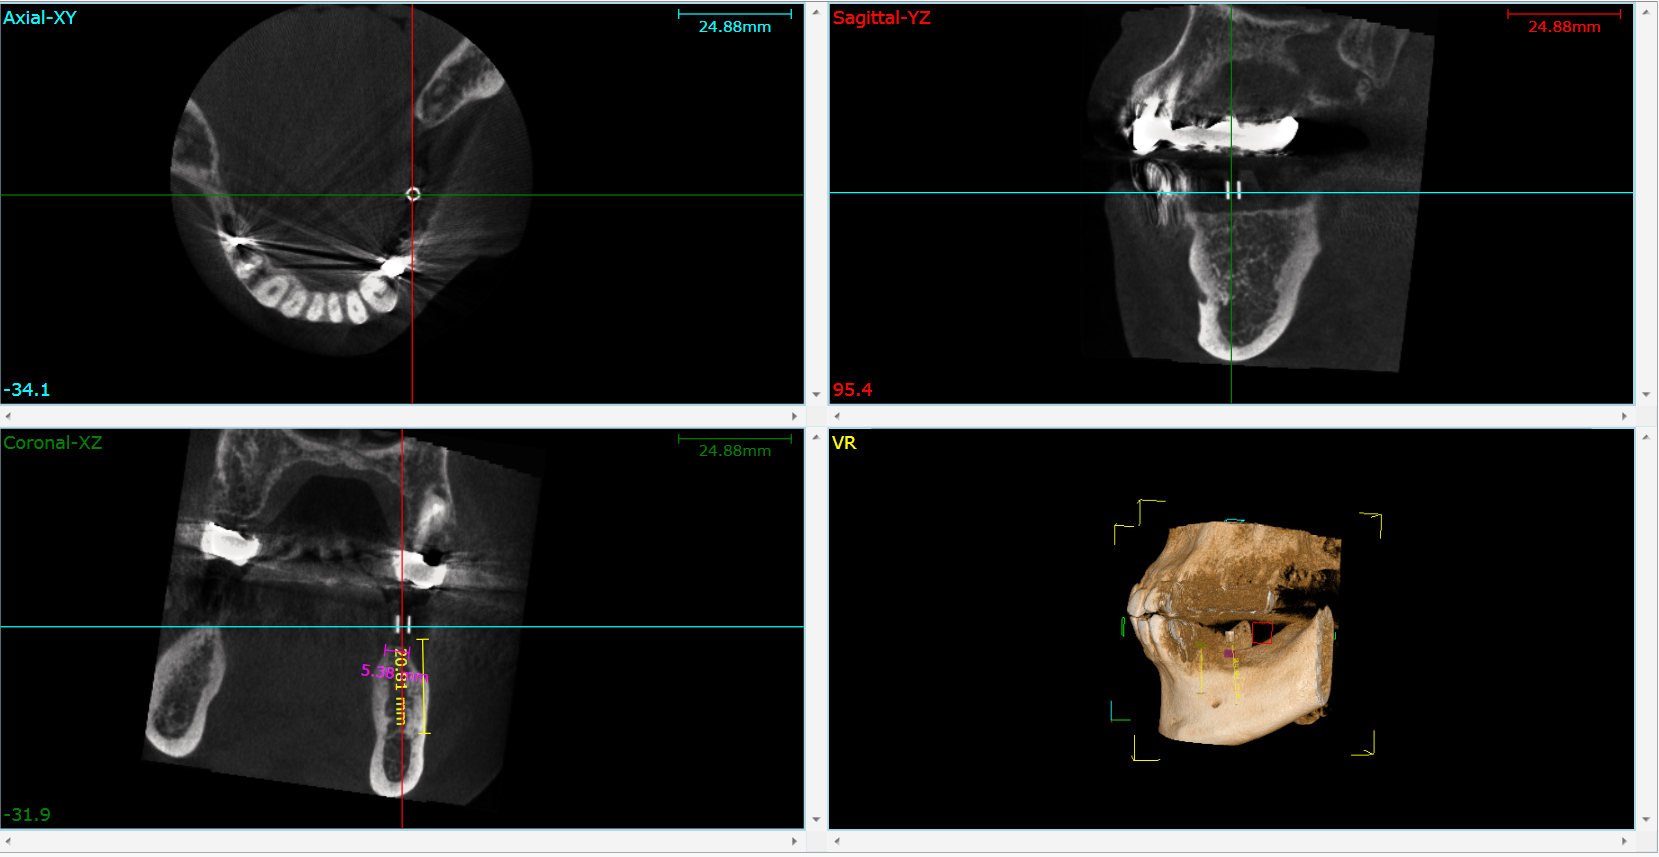

インプラントについて知ろうーその37 インプラントはCTが必須ー

インプラントを施術するにあたって必須ともいうべきものがCT

(Computed Tomography;コンピューター断層撮影)です。

歯科ではレントゲン撮影はありますが、骨の形をある程度知ることは

できますが、立体的な形を把握することはできません。